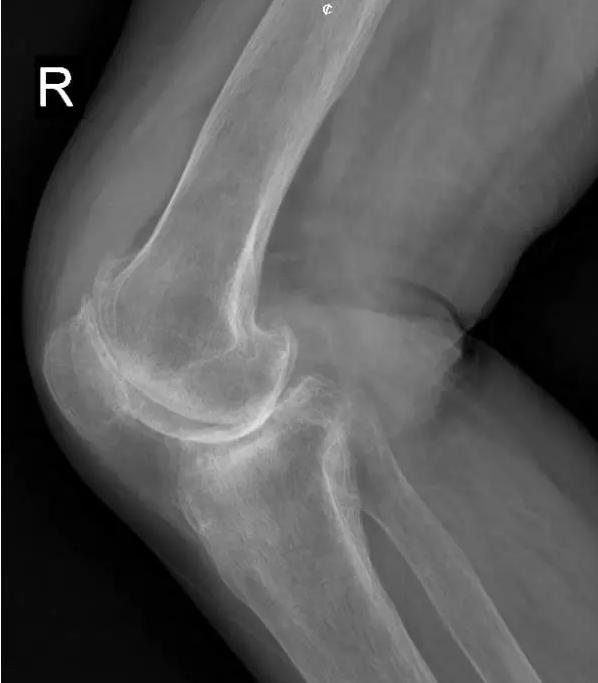

中期:骨关节炎表现为膝关节持续性疼痛,活动后或上下楼梯时加重,压痛明显; X线片上可见增生的骨赘,关节间隙出现狭窄,多为不对称性狭窄。

晚期:骨关节炎表现为膝关节明显疼痛,休息后常无缓解,伴有活动受限,可并发畸形,X 线片可见关节周围有明显的骨赘形成,或可见游离体,关节间隙明显狭窄,甚至消失。

术前片: